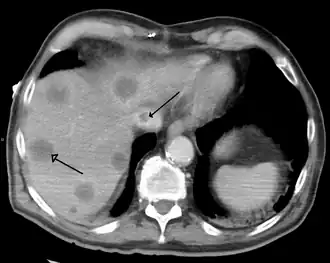

- Primary liver cancer most commonly manifests as hepatocellular carcinoma or cholangiocarcinoma; rarer forms include angiosarcoma and hemangiosarcoma of the liver. (Many liver malignancies are secondary lesions that have metastasized from primary cancers in the gastrointestinal tract and other organs, such as the kidneys, lungs.)[16]

A previously undiagnosed liver disease may become evident first after autopsy. Following are gross pathology images: